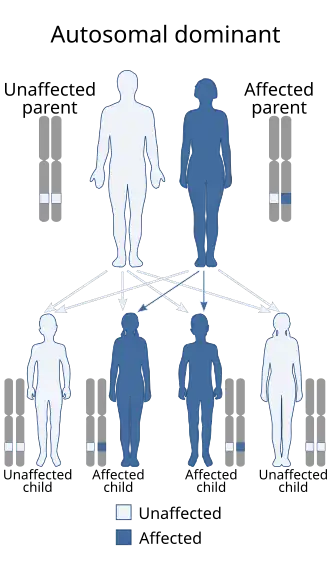

Genetics

Nail–patella syndrome is inherited via autosomal dominancy linked to aberrancy on human chromosome 9's q arm (the longer arm), 9q34. This autosomal dominancy means that only a single copy, instead of both, is sufficient for the disorder to be expressed in the offspring, meaning the chance of getting the disorder from an affected heterozygous parent is 50%. The frequency of the occurrence is 1/50,000. The disorder is linked to the ABO blood group locus.[14]

It is associated with random mutations in the LMX1B gene. Studies have been conducted and 83 mutations of this gene have been identified.[15][16][17]